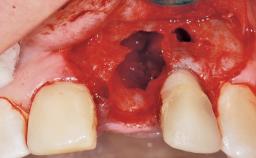

A 30-year-old female patient had lost tooth 21 and was referred to our clinic for consultation and treatment. Due to advanced apical infection, tooth 21 had been extracted two months earlier at another clinic and an acrylic-resin tooth had been bonded to the adjacent teeth. The patient desired implant treatment to avoid any damage to the adjacent natural teeth. While the patient had no history of any systemic disorder, she was a heavy smoker and exhibited medium to advanced periodontitis in the entire jaw. After the initial treatment to achieve a pocket probing depth of less than 4 mm and no bleeding on probing, a decrease in the height of the papillae mesial and distal to the extraction site and overall gingival recession were observed.

Soft Tissue Anatomy Intact Defective

Bone Volume Horizontally and vertically sufficient Horizontally deficient Deficient vertically or deficient vertically AND horizontally

Bone Volume Deficient horizontally, requiring prior grafting